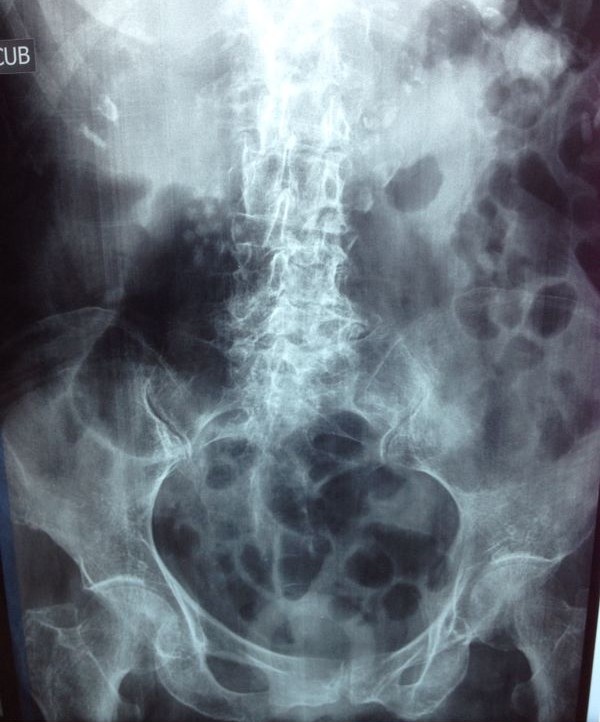

Presence of stones (gallstones) in the duct that carries bile from the liver and gallbladder to the intestine.

These stones are formed by bile pigments and calcium or cholesterol salts.